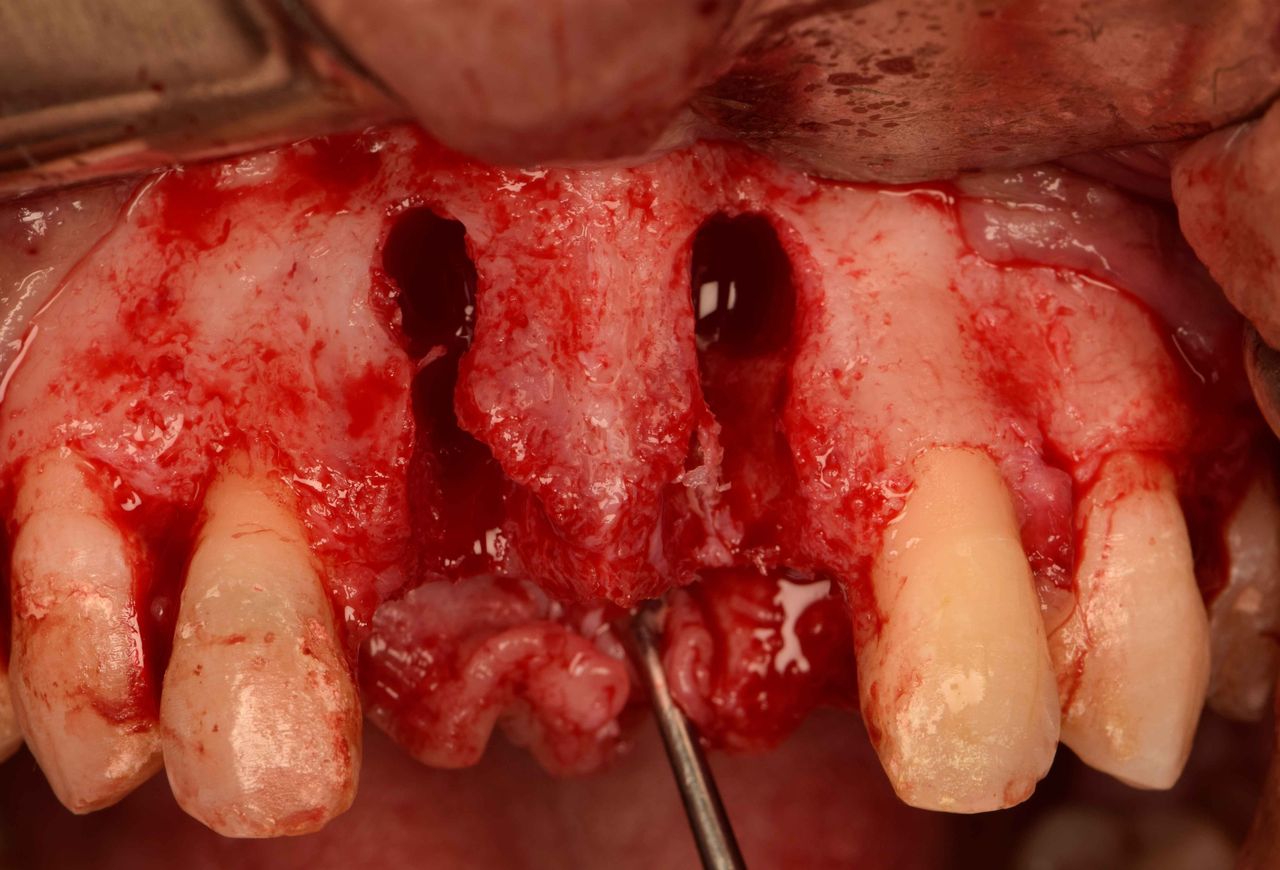

Management of type II sockets in the esthetic zone is challenging. Many treatment modalities have been proposed. Unlike rushed treatments, the conservative approach of early placement after 8 weeks following tooth extraction proposed by the ITI remains the standard in my humble opinion with the least complications and predictable outcome. This video shows a step-by-step approach for managing a case of two central incisors that had multiple failed root canal treatments. The patient presented with chronic fistulous tracts oozing pus and was looking for a permanent solution for his ongoing problem.